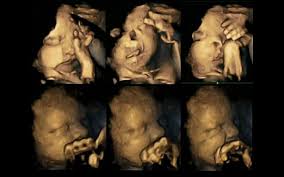

Εναν συγκλονιστικό τρόπο για να αναδείξουν τις βλαβερές συνέπειες του καπνίσματος για τα έμβρυα βρήκαν οι επιστήμονες: τις κινήσεις ενόχλησης που κάνουν με τα μικροσκοπικά τους χέρια τα ίδια τα έμβρυα, όπως αυτές εικονίζονται σε υπερηχογραφήματα με τετραδιάστατη απεικόνιση (4D).